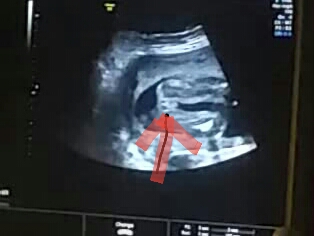

На УЗИ в 14+3 (фото ниже) нам пророчили девочку)) стрелочкой отмечено куда глядеть)

Сегодня мне сомнительно сообщили о мальчике) - мол срок маловат,толком не видно.

поэтому пока у нас 1/1)))) и крашу кружек обратно в желтый и хожу в неведении)